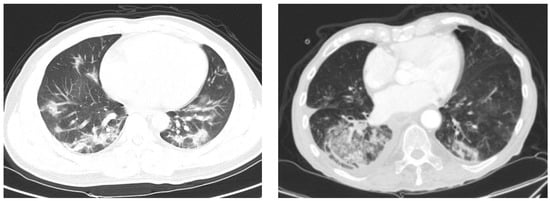

- Parekh, M.; Donuru, A.; Balasubramanya, R.; Kapur, S. Review of the chest CT differential diagnosis of ground-glass opacities in the COVID era. Radiology 2020, 297, E289–E302. [Google Scholar] [CrossRef] [PubMed]